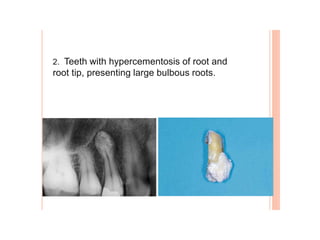

Dental caries, also known as tooth decay, is caused by certain types of acid-producing bacteria in the mouth that damage tooth structures when fermentable carbohydrates like sugar are present. It can lead to pain, tooth loss, infection, and in severe cases, death. While early signs may include white spots on teeth, untreated caries will form cavities. Risk factors include poor oral hygiene, frequent sugar consumption, dry mouth, and tobacco use. Treatment involves removing decay, restoring teeth, or extracting severely damaged teeth to prevent further destruction and infection. Preventive measures include proper brushing, flossing, limiting sugar intake, dental sealants, and fluoride therapy.